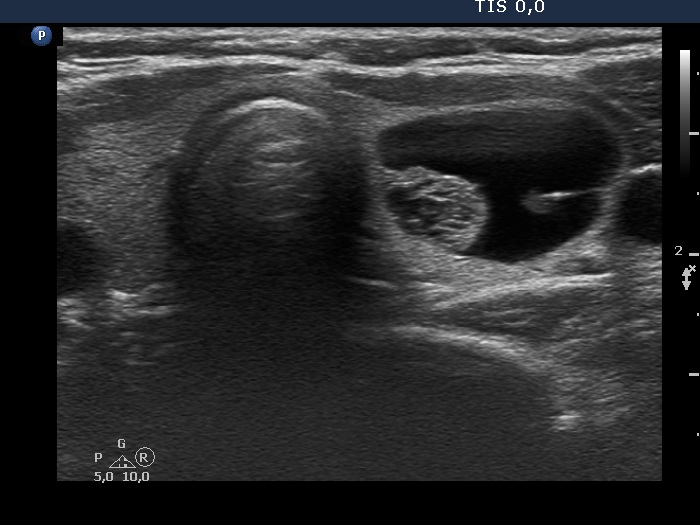

Right lobe, longitudinal scan

Left lobe, another transverse scan. This is a peripheral-type cyst.